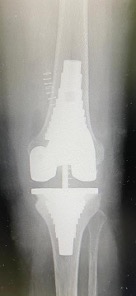

Revision total knee arthroplasty (rTKA) poses significant challenges in achieving stable, long-term fixation, particularly when residual bone stock is compromised1. The integrity of the metaphyseal region is crucial for attaining optimal stability in a revision construct. This area, due to its rich vascularization and reduced susceptibility to surgical damage compared to the epiphyseal bone, facilitates cement interdigitation and implant osteointegration, contributing to superior initial fixation and prolonged implant survival2. In cases with substantial bone defects, two commonly adopted global approaches leverage these properties: the use of cones and metaphyseal sleeves3. These constructs differ significantly. Cones, which serve as fillers, are used to fill defect sizes and enhance the fixation of cemented implants without structural integration with other components. In contrast, metaphyseal sleeves are integrated parts of the implant, providing primary and direct fixation while aiding in load transfer from the revision components to the metaphyseal region. Additionally, metaphyseal sleeves offer the potential for bony biologic fixation, improving rotational stability and protecting epiphyseal fixation. Compared to fluted cylindrical stems, metaphyseal sleeves are more effective in achieving these objectives4. Clinicians typically use stems initially to stabilize sleeves (Figure 1), but there is an increasing trend toward using sleeves without stems (Figure 2). However, studies on this approach are limited by small sample sizes, lack of control groups, and short follow-up periods. Importantly, there is currently no consensus on the necessity of using stems with metaphyseal sleeves. This systematic review aims to summarize the contemporary literature to determine whether using metaphyseal sleeves without stems in rTKA is a valuable option.

Figure 2. Stemless sleeve configuration in revision total knee arthroplasty.